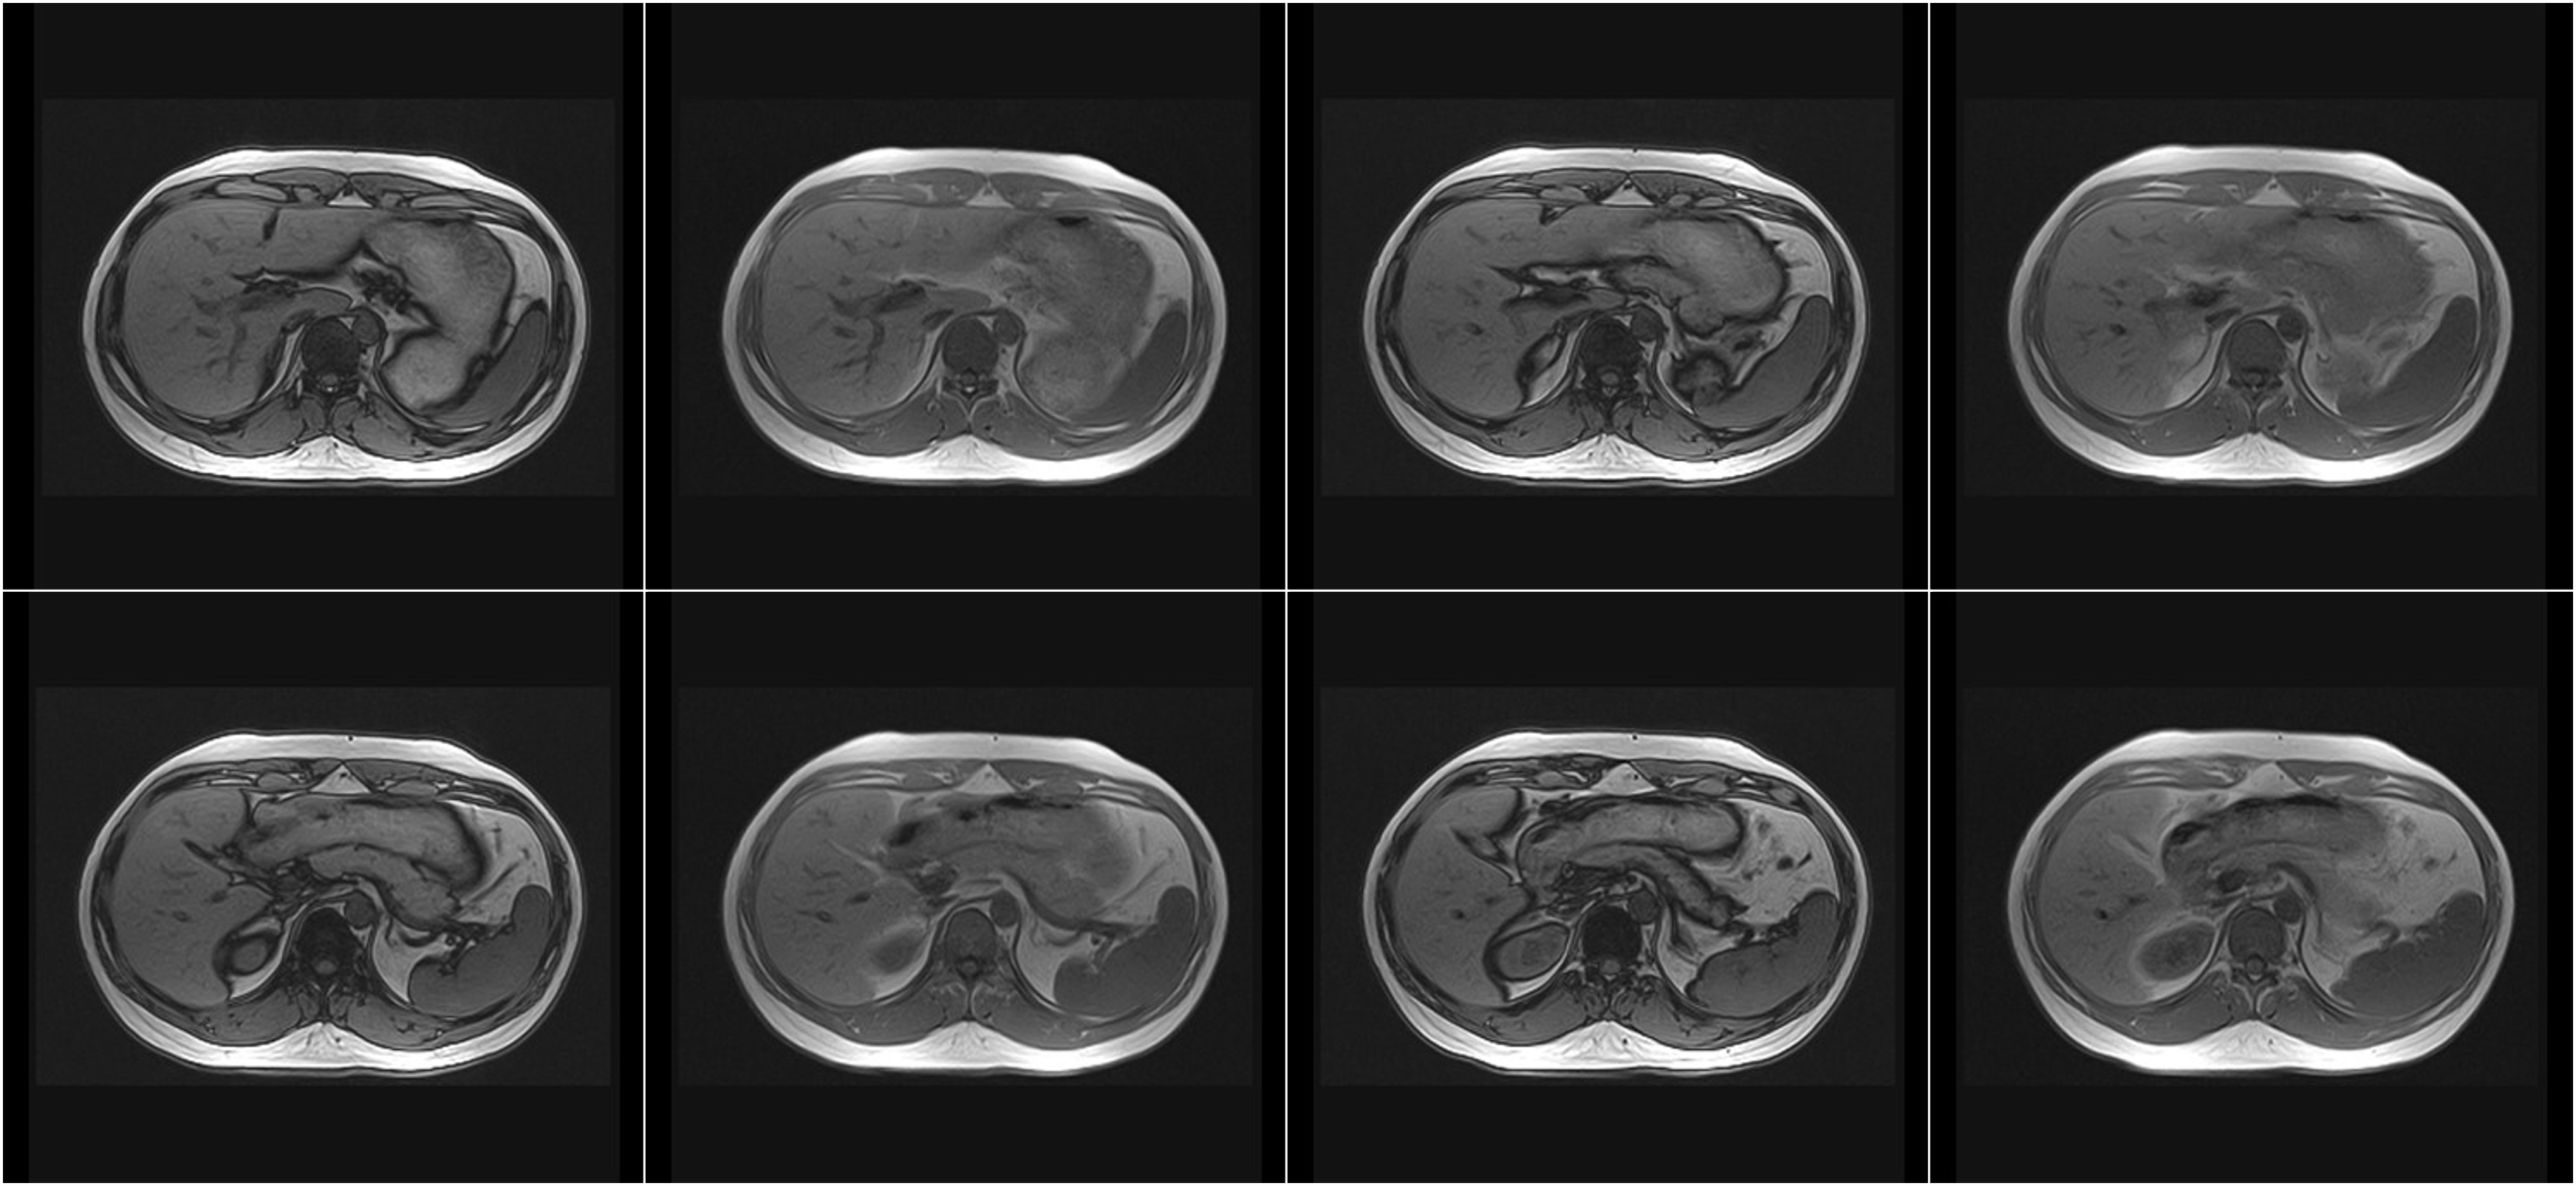

Hình ảnh lâm sàng